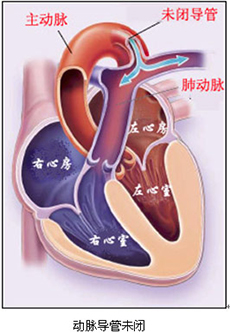

新生儿持续肺动脉高压(PPHN)

疾病介绍:新生儿持续肺动脉高压是由多种病因引起的新生儿出生后肺循环压力和阻力持续增高,而发生心内水平(通过卵圆孔)和(或)动脉导管水平的右向左或双向分流,…【详细】